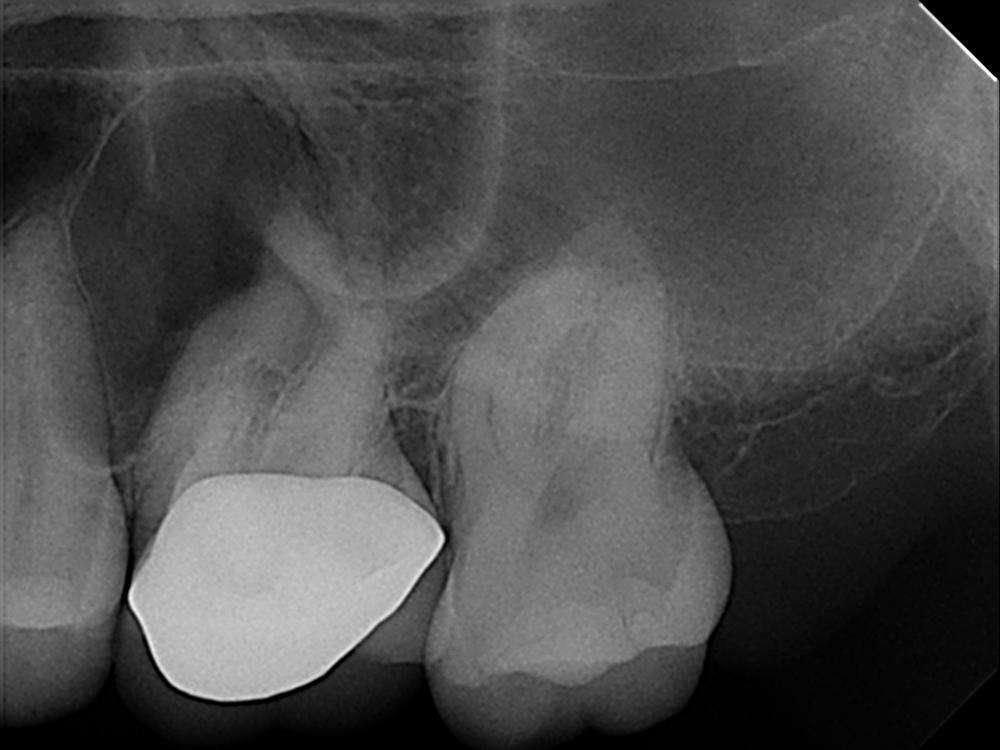

Ich bin Endodontologin aus Atlanta, Georgia, und habe meine Fachausbildung an der University of Pennsylvania absolviert und meinen Abschluss im Jahr 2013 gemacht. Ich möchte Ihnen diesen Fall eines Molaren Nummer 14 einer 33-jährigen Patientin mit irreversibler Pulpitis und symptomatischer apikaler Parodontitis vorstellen. Dieser Fall wurde diagnostiziert und mit Diamantbohrern ein Zugang durch die Krone hergestellt. Dann wurde mit Natriumhypochlorit gespült.

Wenn man einen Fall wie diesen sieht, fragt man sich, welche Feile man dafür verwenden soll ? Wie soll ich diesen Kanal behandeln, ohne dass die Feile bricht ?

Zuerst habe ich versucht, die Durchgängigkeit der Kanäle zu erreichen, ich habe die Durchgängigkeit des distalen mesiobukkalen Kanals und des distalen Kanals mit 10er Feilen gemacht und mich dann auf eine 15er-Feile hochgearbeitet. Ich habe diesen Fall mit einer SX-Feile instrumentiert, um die Öffnungen zu öffnen, und dann reichlich mit Natriumhypochlorit gespült. Ich habe angefangen, die EdgeEndo-Feilen mit der Crown-Down-Technik zu verwenden. Wenn man diese Art von Kanälen sieht, die sehr gekrümmt sind, möchte man den oberen Teil des Kanals ein wenig aufweiten, damit die Feilen leichter nach unten gleiten können und weniger an den Wänden hängen bleiben. Ich fing mit der Crown-Down-Technik von 40 auf 25 an, und ging dann durch bis zu 40 bei der mesiobukkalen, bei der distalen, und bis 45 bei der palatinalen.

Als ich das Röntgenbild machte, um zu sehen, wie die Konusse passen, bemerkte ich, dass ein Kanal fehlte, also benutzte ich das DVT, um den MB2Kanal zu finden. Bei all dem habe ich natürlich, während ich meine EdgeFiles verwende, auch Gleitmittel, RC-Präparate für die Instrumentierung verwendet, und ich habe auch viel Natriumhypochlorit zum Instrumentieren verwendet.

Vor der Konusanpassung spüle ich mit Ultraschall unter Verwendung von Natriumhypochlorit, EDTA und Chlorhexidin. Ich habe meine Konusanpassung mit dem Edge Gutta Percha und dem AH Plus Sealant gemacht.

Ich fuhr mit der Instrumentierung bis 35 bei MB2 in der gleichen Reihenfolge fort, unter Verwendung von Natriumhypochlorit, zuerst hinauf bis auf eine Größe von 15 und dann machte ich einen Crown-Down bis auf eine 35. Danach habe ich alles mit Natriumhypochlorit, EDTA, Chlorhexidin gespült und alles mit sterilen Papierspitzen getrocknet und eine Röntgenaufnahme mit Konuspassung gemacht, mit Konus und Alter plus Versiegelung.

Jetzt kann ich Ihnen sagen, dass ich beim Röntgen gesehen habe, dass der MB2 fehlt, also habe ich einen CT-Scan gemacht und bemerkte den MB2 und bemerkte die seltsame ungewöhnliche bukkale Neigung des MB2 zum Gaumen hin, und der MB zeigte wirklich in Richtung bukkal. Es sah fast aus wie die Zunge einer Schlange. Ich dachte, oh wow, das war das, wonach ich gesucht habe. Den MB2 habe ich bei der zweiten Sitzung gefunden. Ich habe vorher alles mit Calciumhydroxid verschlossen, bei der zweiten Sitzung fand ich dann MB2.